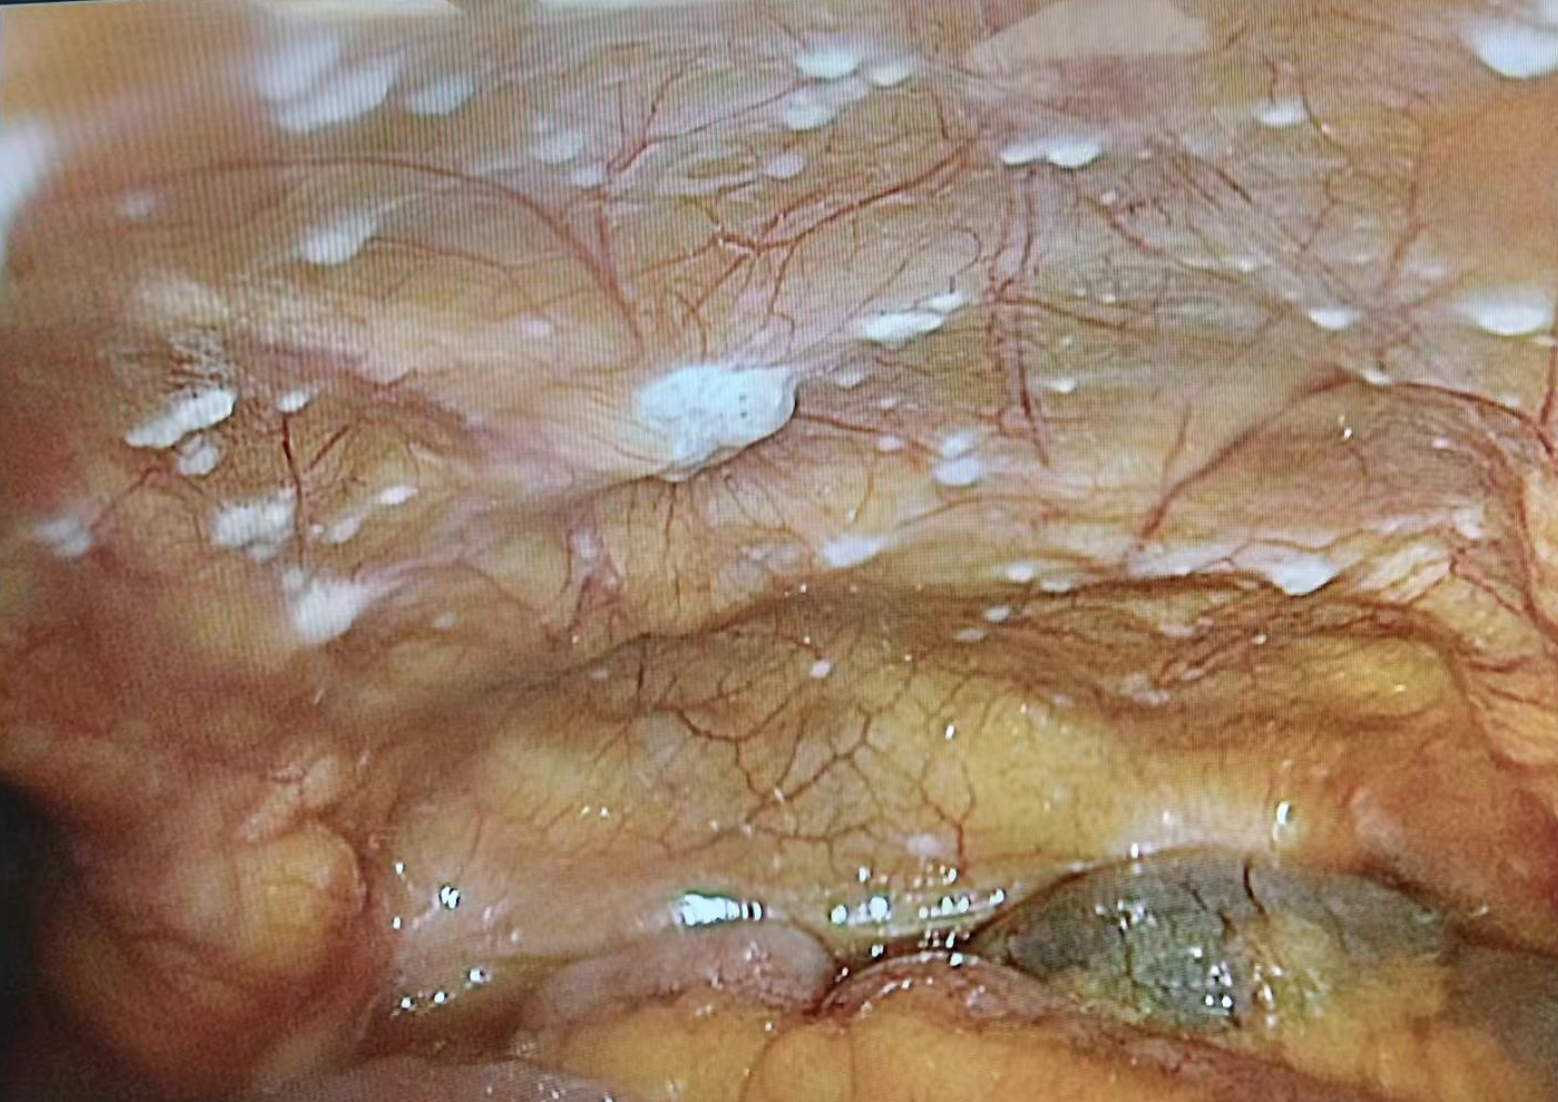

open-close手术:术前通过CT可以大致发现肿瘤局部的浸润情况和远处转移情况。但是CT具有一定的局限性,部分微小的转移在CT上不能显示,以至于在术中探查后才能发现,比如腹腔种植转移(图2),当看到这种情况时,除非存在梗阻或则肿瘤出血,原则上不手术,需要先接受治疗;

图2:白色结节为肿瘤种植转移病灶